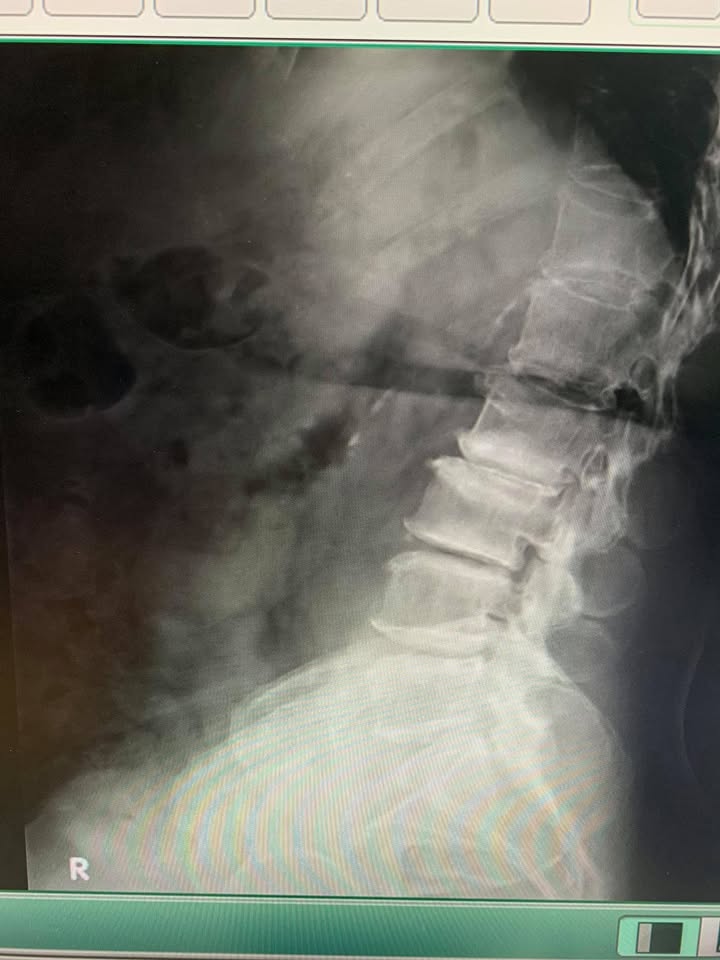

這兩張圖可以講半小時以上⋯⋯⋯⋯⋯

一個脊椎初診患者,耐心聽完病史,看過所有檢查片子,把資料印出來給患者,觸診、理學檢查、制定醫療計畫表,然後敘述針刀醫學原理與幾次內應該看到效果、風險評估、排床治療、衛教⋯⋯⋯⋯⋯⋯